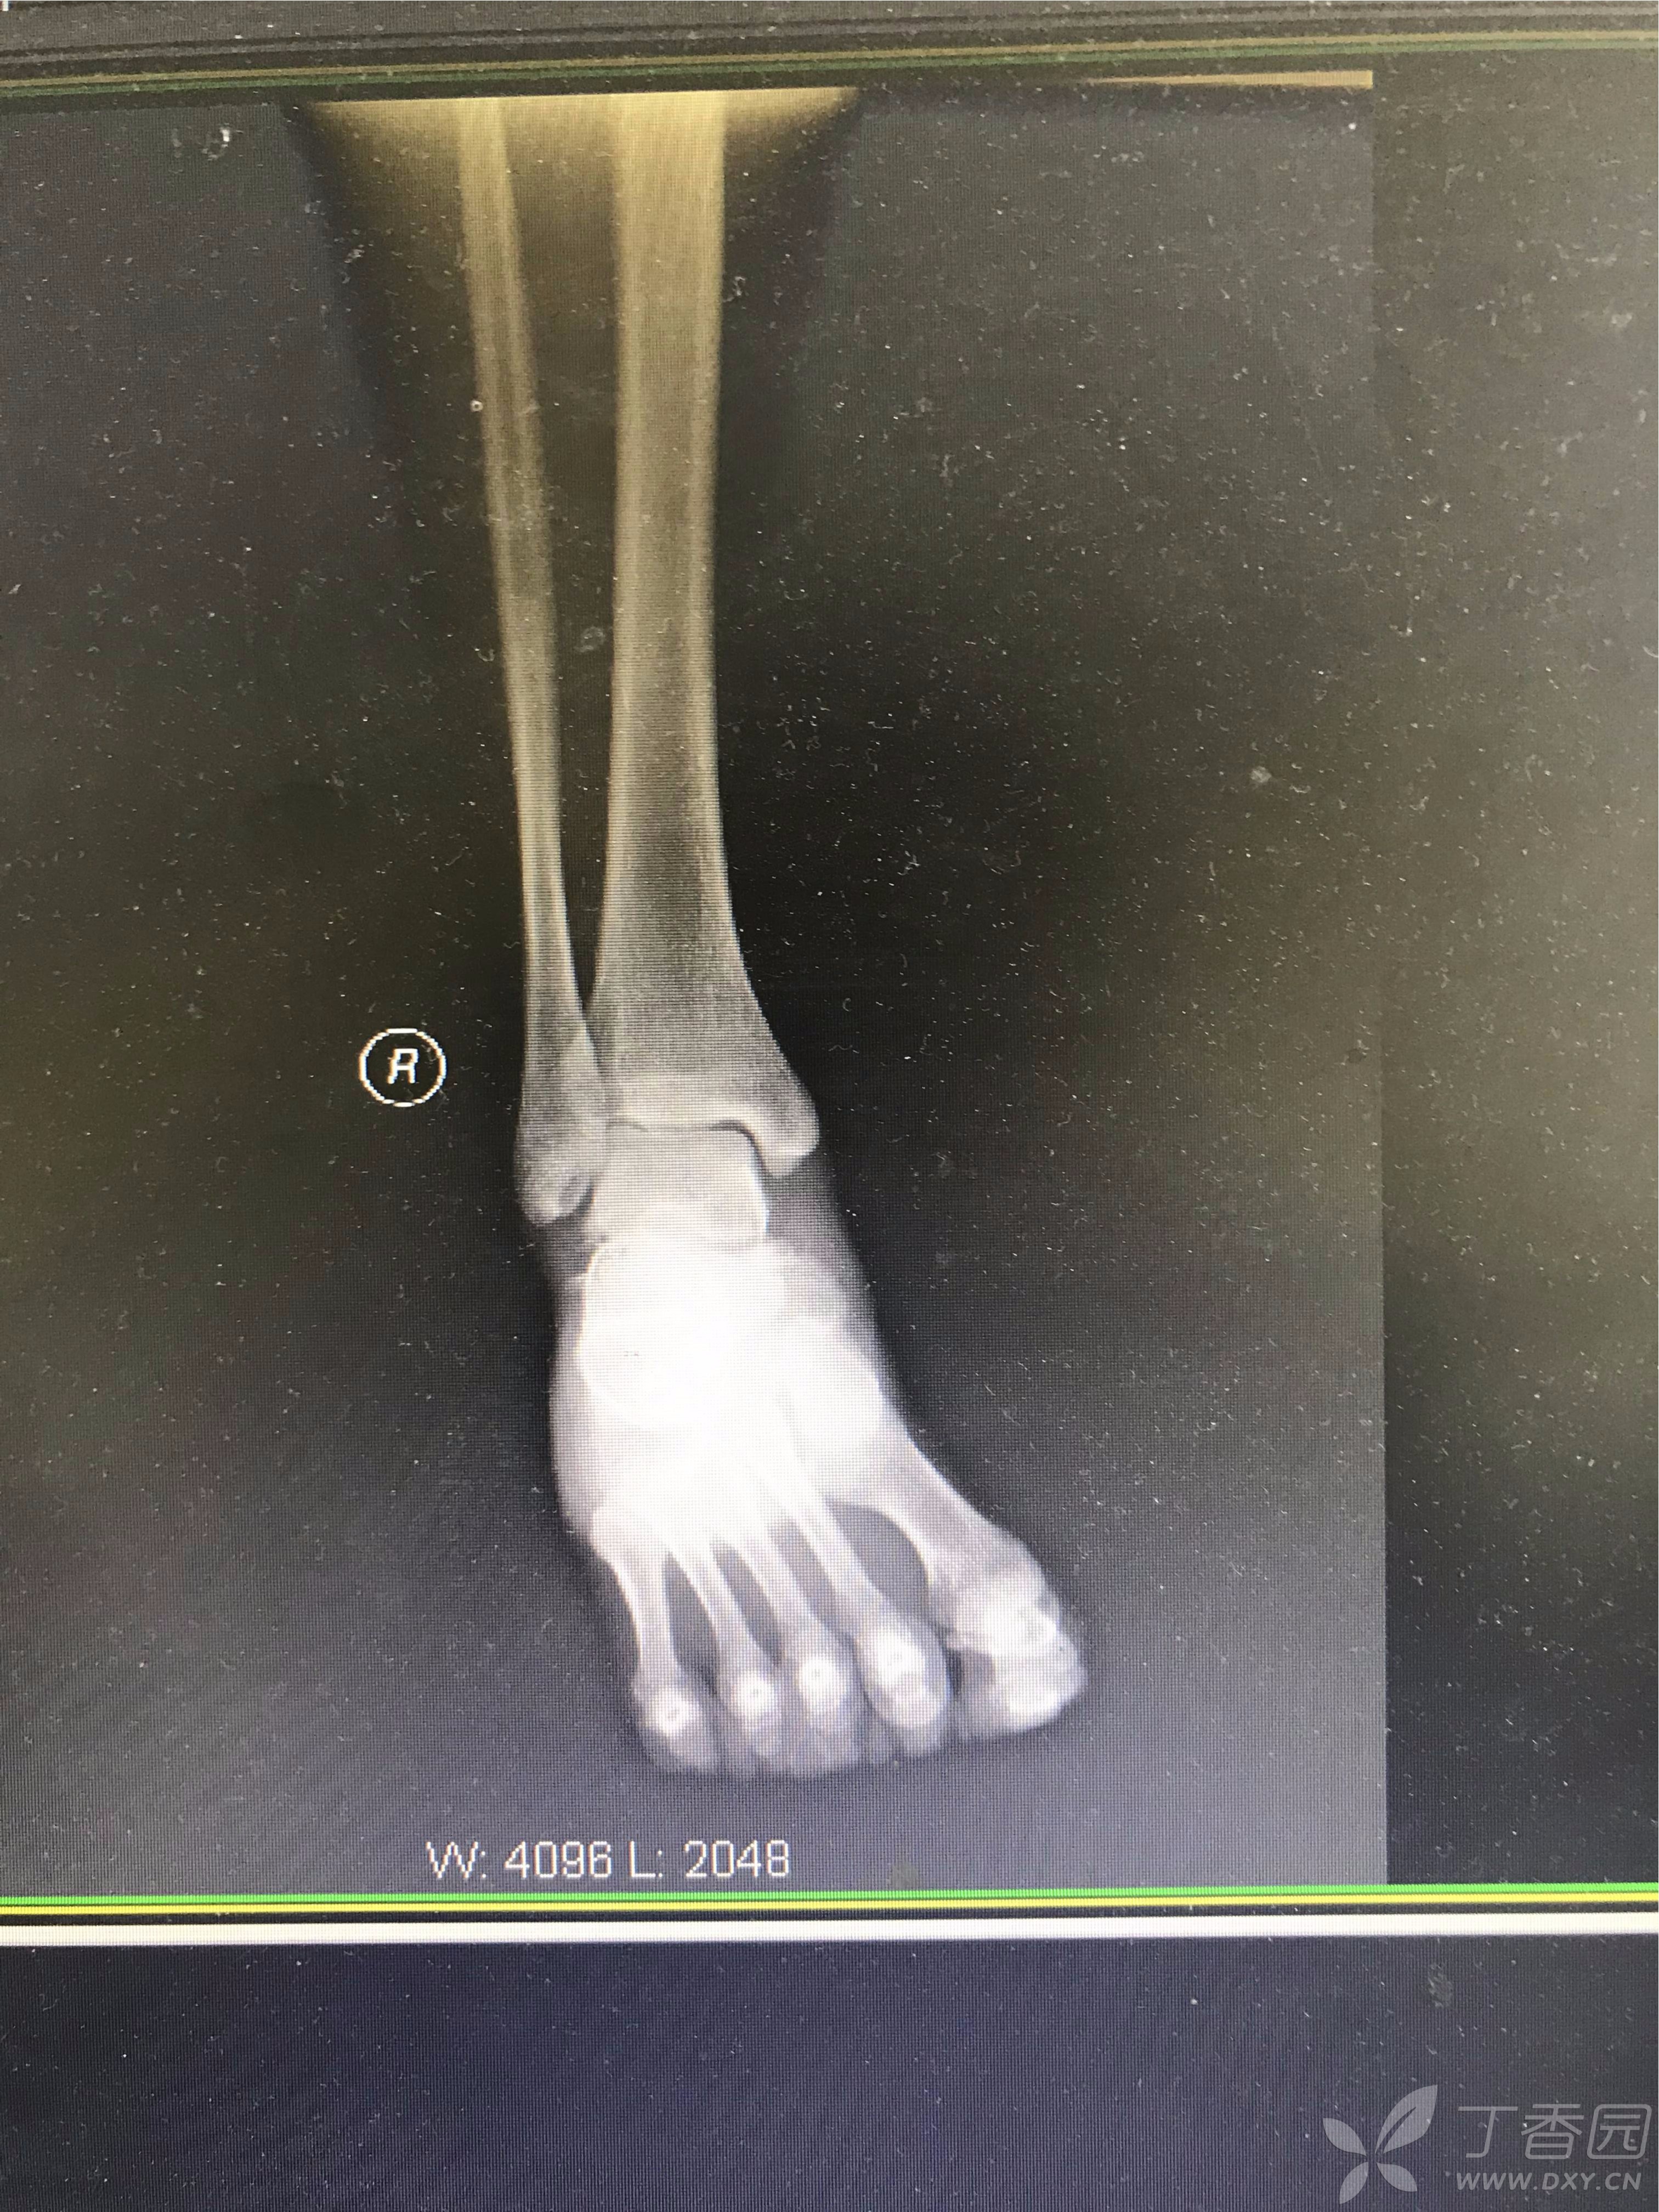

一例罕见的距下关节脱位